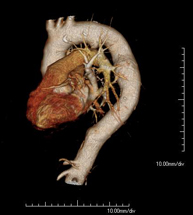

- Abdominal aorta CT angiography

A non-invasive diagnostic test that involves studying the abdominal aorta by obtaining high-definition anatomical images using CT (computed tomography) equipment and iodinated contrast. With the aid of workstations specialised for arterial studies, the image quality supports 2D and 3D reconstructions. It is indicated in patients with vascular disease (atherosclerosis), aortic aneurysms, abdominal pain of possible vascular origin, pre-surgical studies of lesions adjacent to the abdominal aorta as a vascular ‘map’, etc. Information obtained non-invasively is indispensable for patients requiring percutaneous or surgical processing. In patients who only require tracking of vascular lesions, this technique is the non-invasive technique of choice, together with MRI angiography.